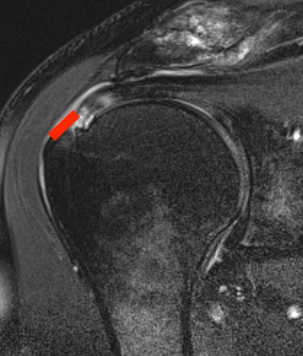

Bursal Sided